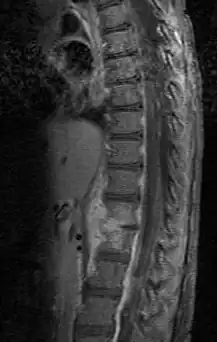

| Discitis in a 2 year old child. | |

Discitis, or diskitis, is an infection in the intervertebral disc space that affects different age groups. Symptoms include severe back pain, leading to lack of mobility. In adults, it can lead to severe consequences, such as sepsis or epidural abscess, but it can also spontaneously resolve, especially in children under 8 years of age. Discitis occurs post-surgically in approximately 1–2 percent of patients after spinal surgery. There is debate as to the cause. Diagnosis is usually apparent on MRI, although plain X-rays and CT examinations can be suggestive. Treatment is difficult and usually includes antibiotics. Reducing the mobility of the affected region is an occasionally recommended solution, but changes from case to case.[1]

Diagnosis is usually apparent on MRI, although plain X-rays and CT examinations can be suggestive. The MRI will reveal air changes in the disc and possibly even external involvement involving the bone or epidural regions. A biopsy may be performed and helps with diagnosis in some cases but often an organism is not obtained. C-reactive protein levels and ESR levels will be elevated and are useful for treatment. The white blood cell count may be normal.[5][6]